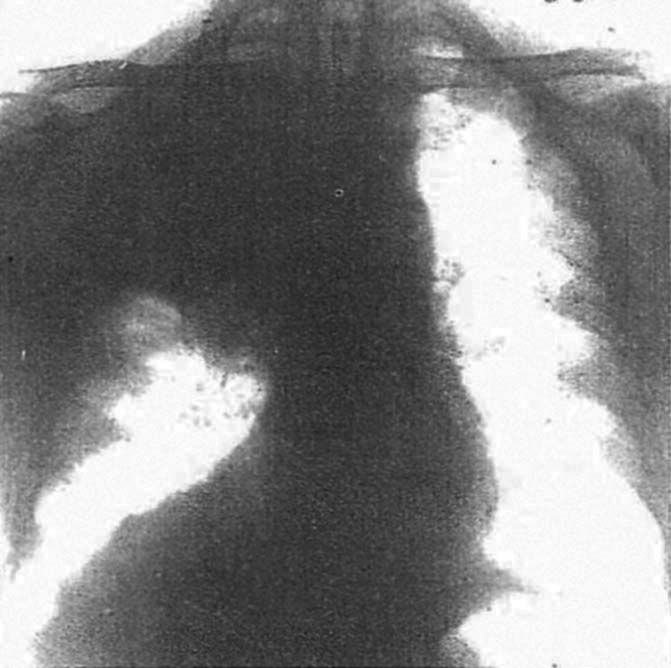

図12. 右肺門部肺癌.右上肺野に均一な陰影があり,陰影の主体は上葉気管支閉塞による閉塞性無気肺および閉塞性肺炎である.その下縁は外側で凹,内側で凸の輪郭を示しており,その特徴的な形状から Golden's inverted S signと呼ばれることがある.

【要旨・解説】肺門部肺癌の基本的なX線所見のひとつである,気管支閉塞による閉塞性無気肺,閉塞性肺炎のX線所見を検討した論文.5症例を供覧して,その陰影の成り立ちを剖検所見,気管支鏡所見と対比しつつ分析している.その結果,肺野に濃厚陰影の拡がりをみる肺癌では,この陰影は腫瘍自体ではなく,基本的に無気肺,肺炎を反映するものであることを明らかにしている.

右肺門部肺癌に右上葉の無気肺を伴う場合,右上肺野の陰影の下縁が,無気肺による上中葉間線と腫瘍の輪郭を連ねた逆S字型を描くことがあり,Golden's (inverted) S signとして良く知られている.この論文では症例Ⅴがこれに相当し(図12),その下縁が外側は凹,内側で凸であると記載しているが,特にS字型という表現は使用していない.Felsonがその教科書 "Chest Roentgenology" (1973)でこの論文を引用して "reverse S shaped curve" と表現したのが初出と思われる.Felsonは側面像,斜位像では,右上葉以外でも同様の所見が見られるとしている.